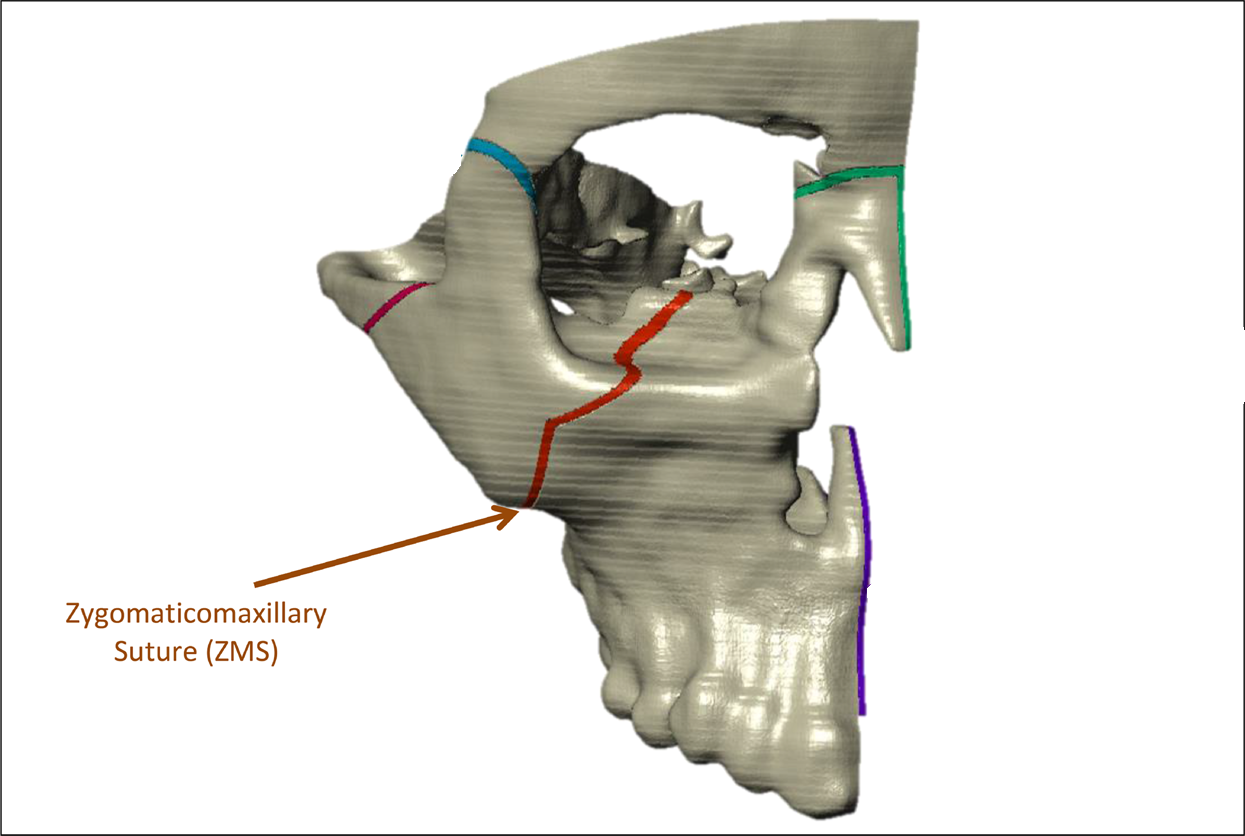

| zygos | zymaticomaxxilary suture

- zygomaticomaxillary & zygomaticotemporal: Zygopushing both laterally and forwards with neck assistance. sessions will be paired with the thumbpulling ones, also lasting 1 min. I haven't found a good source that compiles everything about zygopushing so I might do a thread explaining everything with better depth but if everyone thinks it's cope I might as well gatekeep.